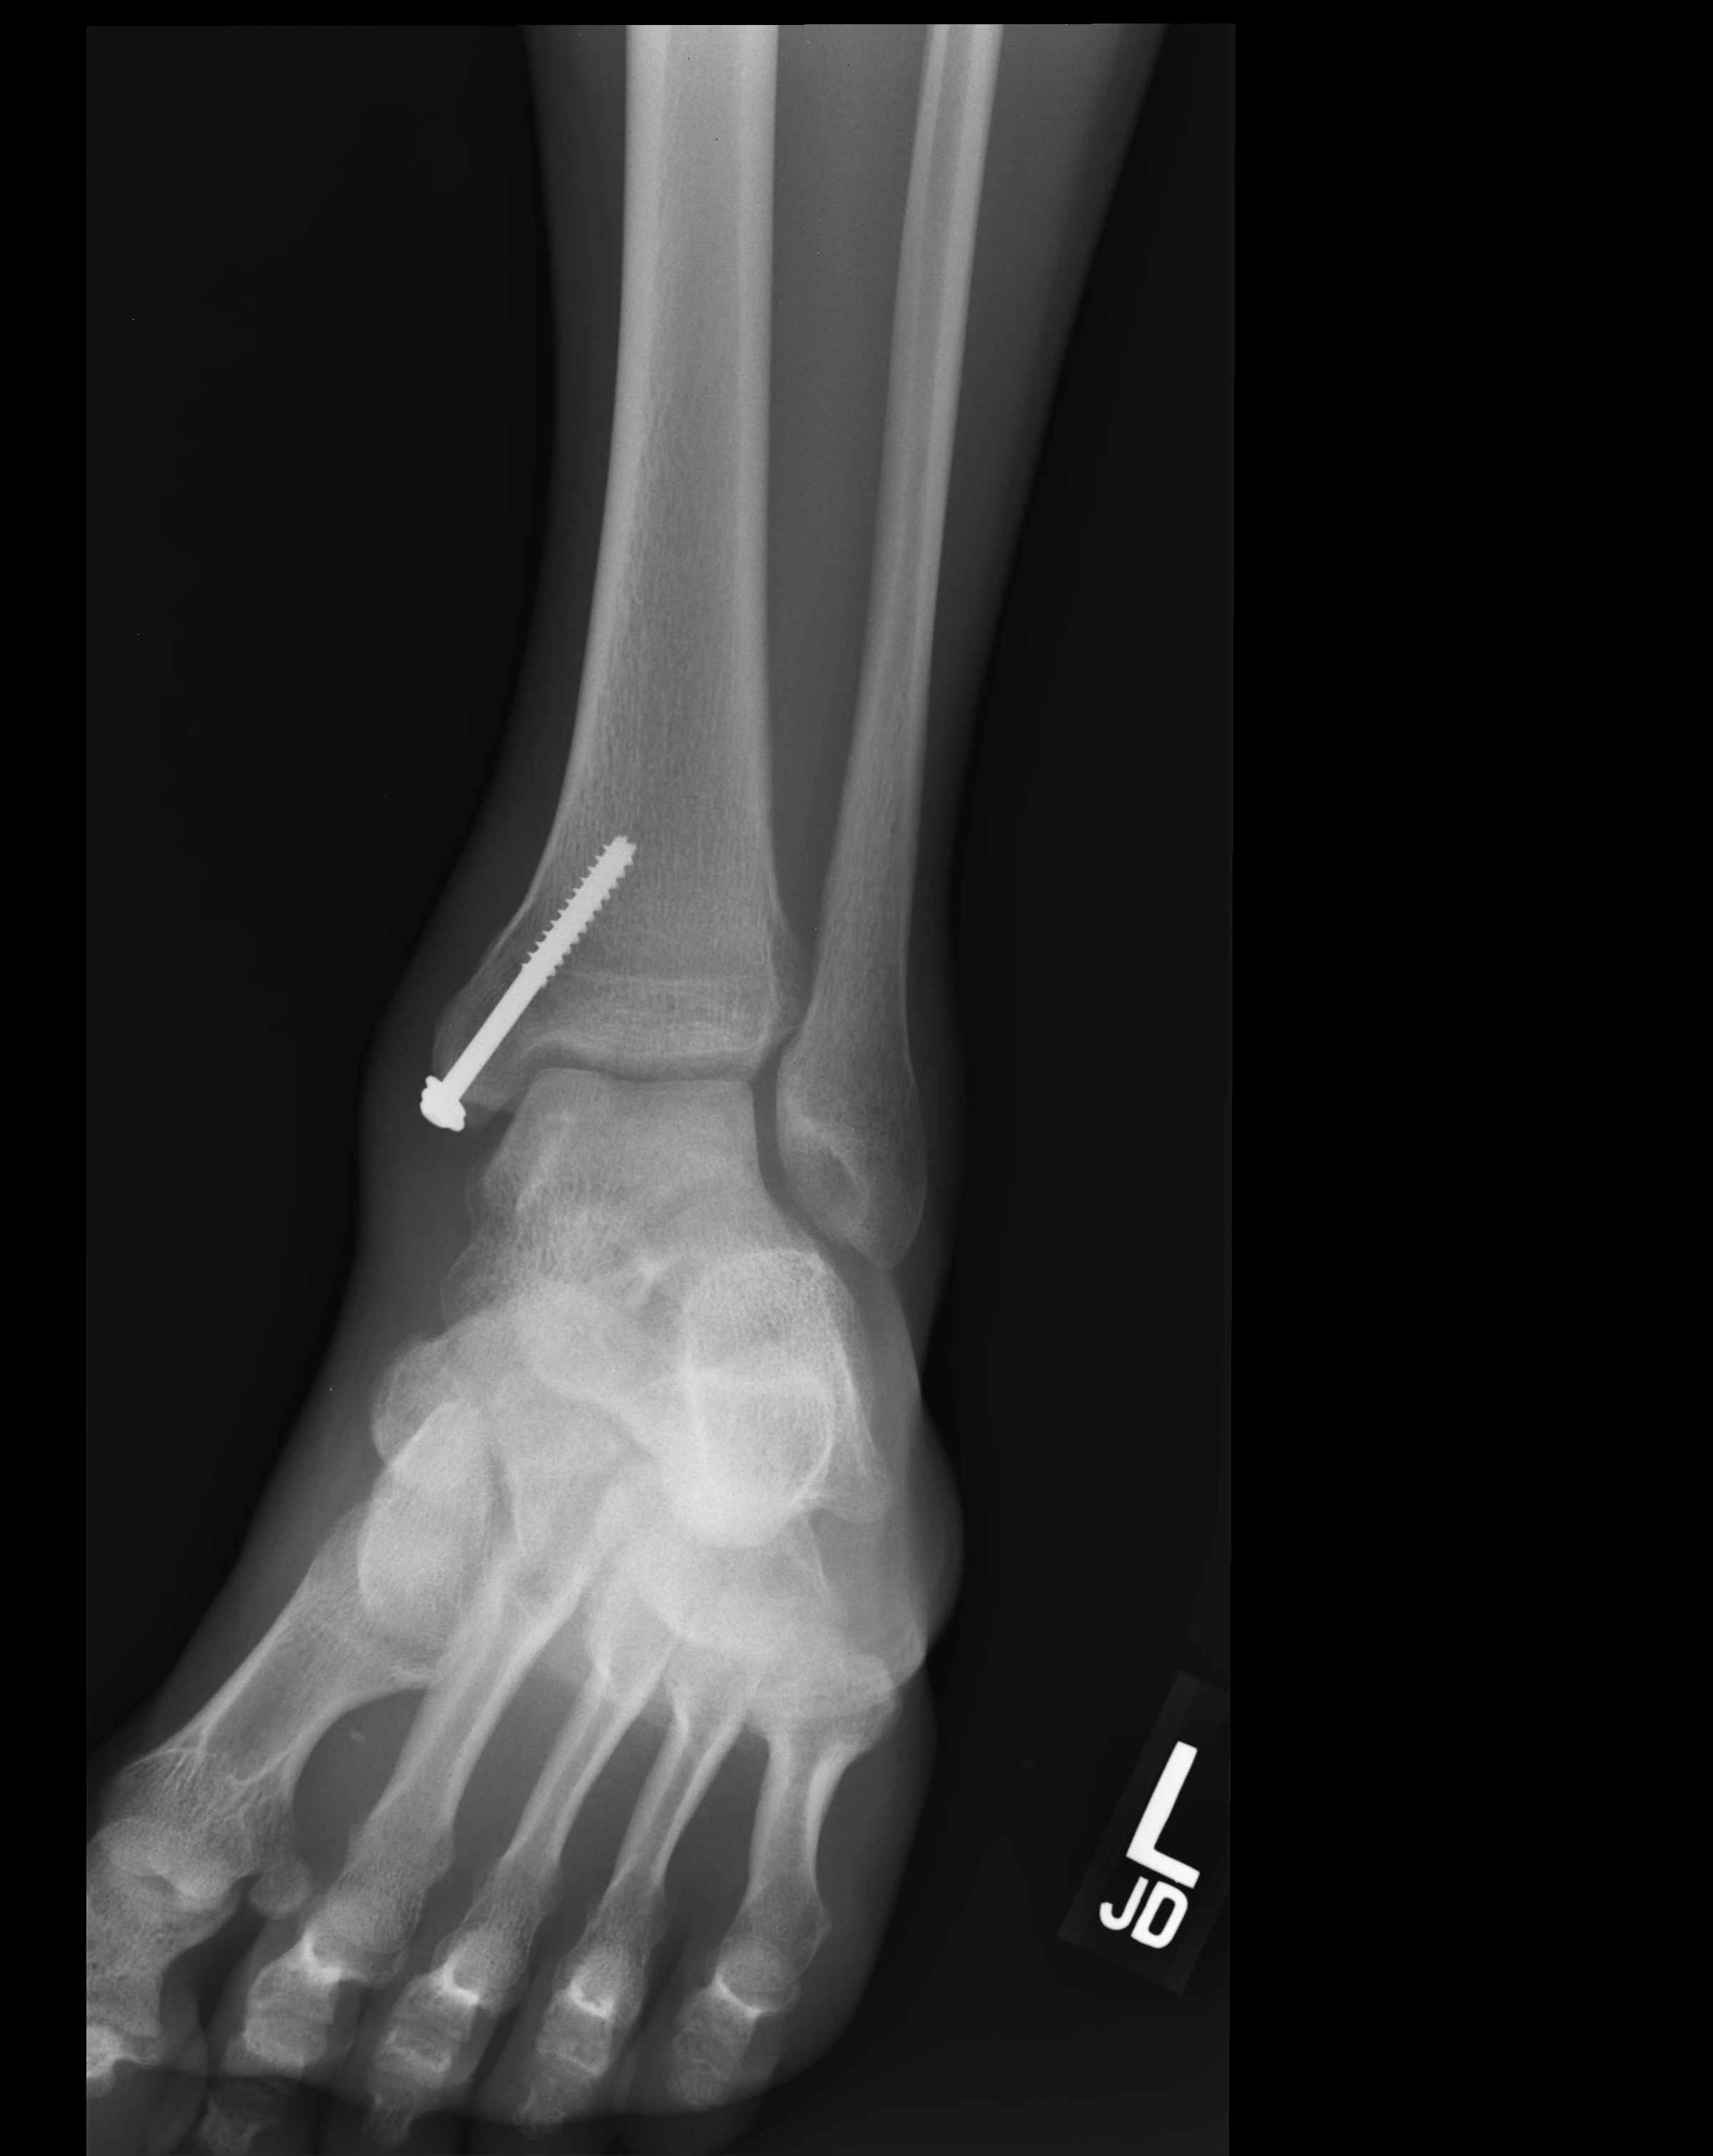

• Osteotomy site: The medial malleolus was cut to access the joint during surgery (can't reach from the front). Two screws were placed. Some irregularity visible at this bone cut

• Medial malleoli osteotomy healed with anatomic alignment and stable hardware

→ The bone that was cut to access the ankle has healed perfectly; screws are solid

• Post-operative changes of ORIF of medial distal tibia with two screws; no residual fracture plane visualized

→ The two screws from surgery are visible; the bone they fixed has healed completely